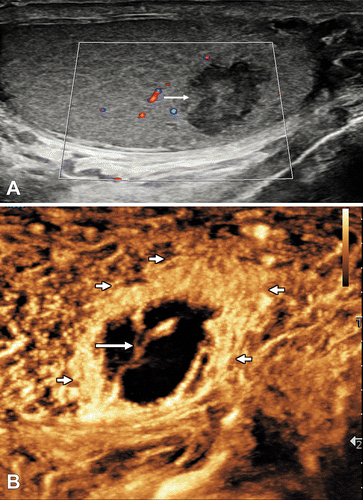

48-летний мужчина обратился с 2-дневной историей внезапно возникшей сильной боли в левой мошонке. (A) Продольное изображение левого яичка при УЗИ в B-режиме демонстрирует смешанную отражающую область (стрелка) без заметной интенсивности сигнала внутреннего цветного допплеровского кровотока. (Б) Продольное УЗ-изображение левого яичка с контрастным усилением демонстрирует окружающее периферическое усиленное усиление (короткие стрелки) и змеевидный сосуд (длинная стрелка), присутствующие в сегментарном инфаркте без усиления. Дифференциация сегментарного инфаркта от абсцесса может быть сложной задачей, потому что оба они могут показать окружающее периферическое усиление и сосудистые проекции ( 2 ); однако маловероятно, чтобы сосудистая структура пересекала абсцесс, как показано в этом случае.

48-летний мужчина обратился с 2-дневной историей внезапно возникшей сильной боли в левой мошонке. При пальпации область была тёплой и припухшей. Больной также жаловался на учащённое мочеиспускание. Первоначальный клинический диагноз: эпидидимит. УЗИ мошонки показало нормальный эпидидимис, гиперемию левого яичка и неоднородную, хорошо очерченную овоидную гипоэхогенную область без внутреннего цветного допплеровского потока размером 22 × 9 × 9 мм ( рис . ). УЗ-изображение с контрастным усилением (CEUS) показало бессосудистое поражение с центральной серпигинозной сосудистой структурой и окружающей гиперемией с использованием метода суммирования усиления ( рис .). Через 6 недель последующее обследование показало, что эта область меньше и менее чёткая, с участками реваскуляризации. Разрешающийся сегментарный инфаркт ( 1 ) был диагностирован на основании данных CEUS ( 2 ).